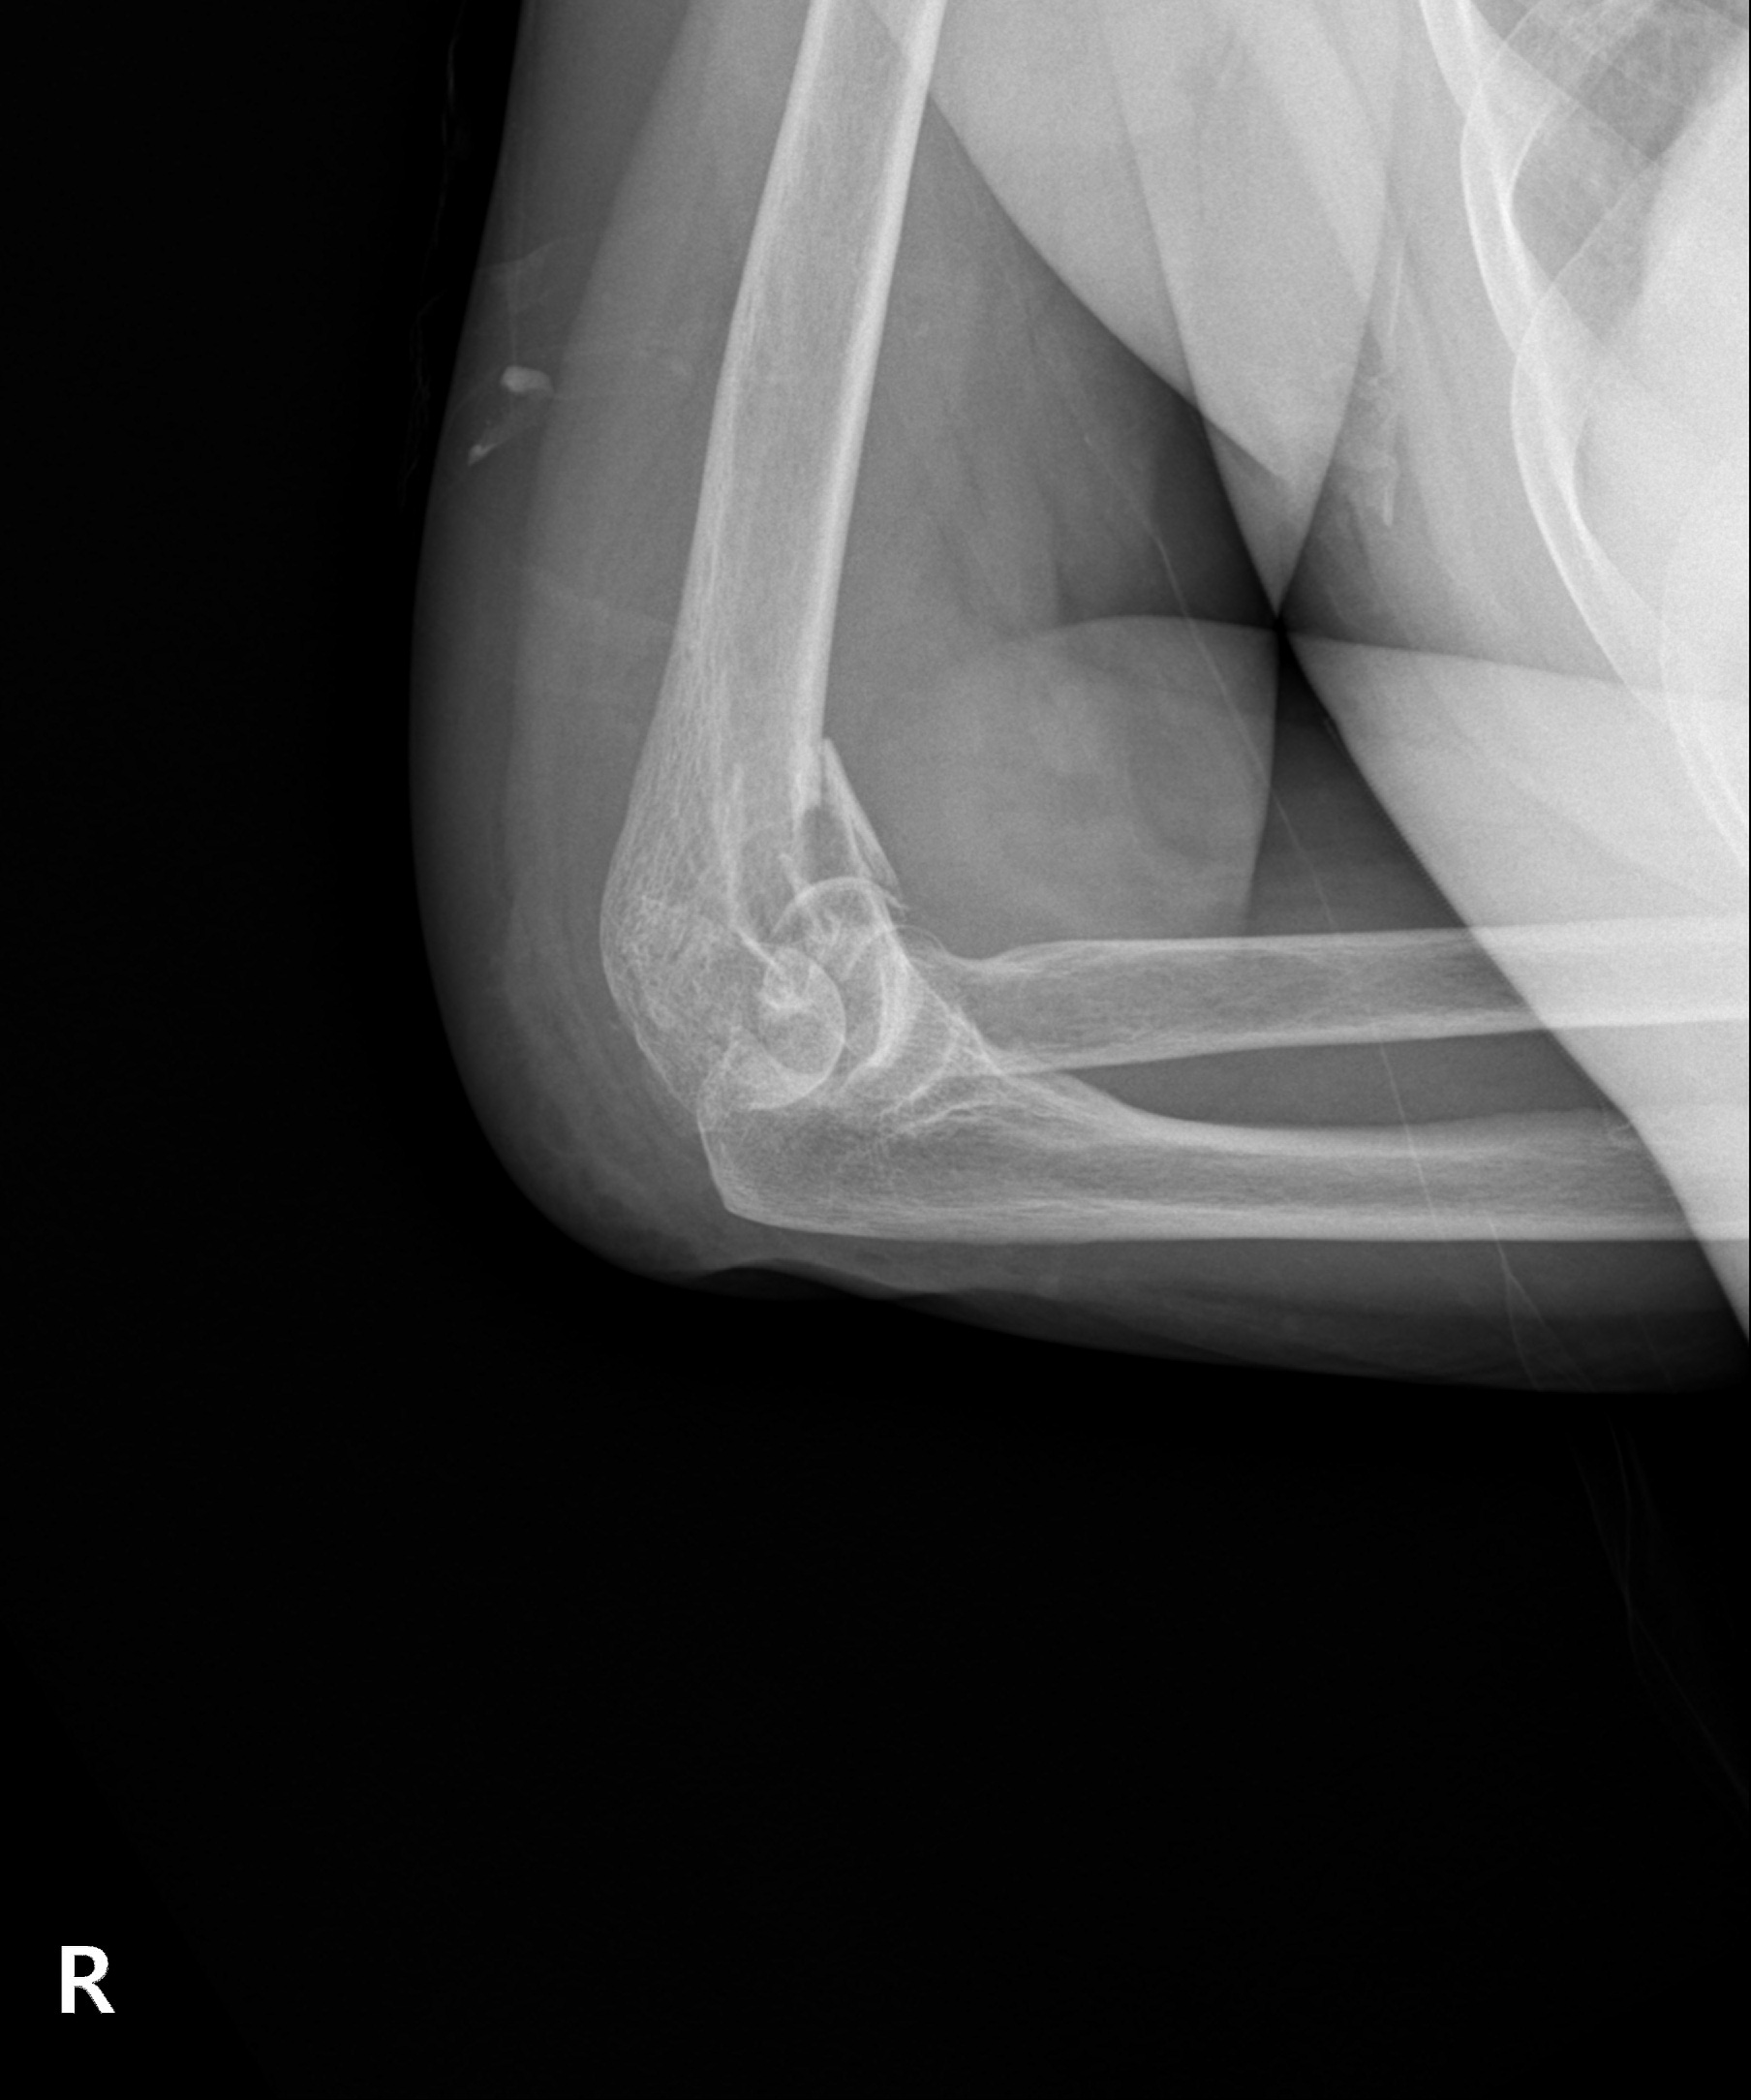

고난도 골절

2023.03.24

2023.03.31

원위 상완골 골절

2022.07.14

2023.02.07